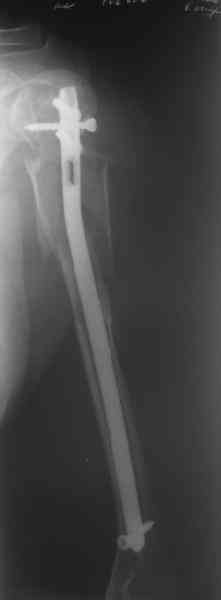

Здесь нет необходимости в серкляже. Вмешиваться на промежуточных отломках приходится, если есть угроза перфорации кожи, или промежуточный отломок попал в фасцию, как пуговица в петлю. В приложении сегментарный оскольчатый перелом плеча в проксимальном отделе, фиксированный больщеберцовым стержнем. Как видите, обошлось без серкляжа. Функция полная.